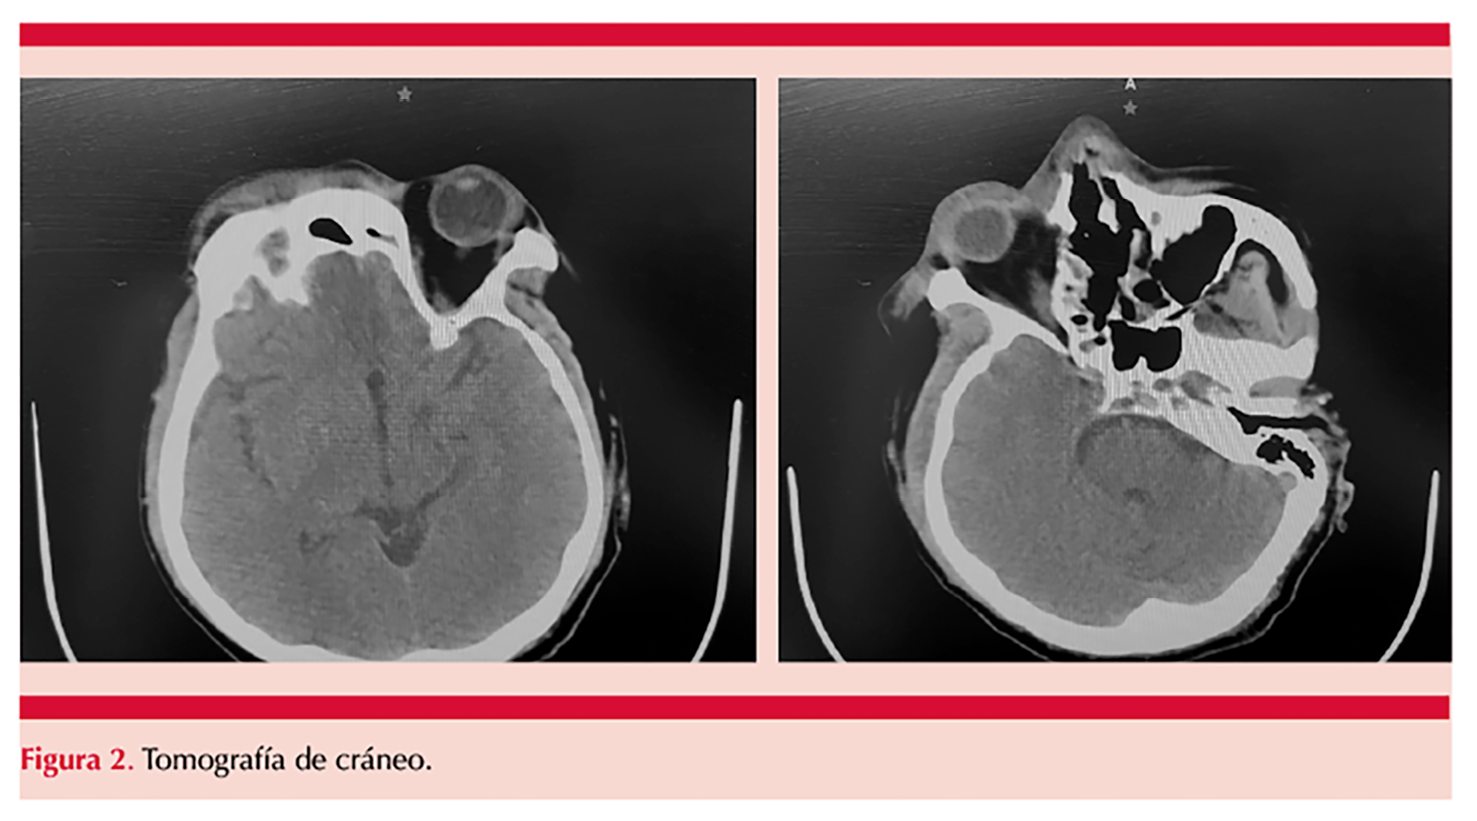

La TAC simple de cráneo mostró los siguientes hallazgos: edema palpebral derecho, engrosamiento mucoso en el seno maxilar derecho, celdillas etmoidales y del seno esfenoidal de manera bilateral, hipotrofia de los cornetes nasales de manera bilateral, desviación septal hacia la izquierda y arteriosclerosis de las carótidas internas bilateral. Figura 2

Los estudios de imagen desempeñan un papel decisivo en la evaluación de la extensión de la enfermedad y en la orientación del tratamiento médico y quirúrgico. En este sentido, es recomendable la realización de TAC o resonancia magnética para confirmar la sinusitis o edema en pacientes diabéticos con dolor facial, signos de sinusitis, proptosis, oftalmoplejía o amaurosis.1 En nuestro caso, la TAC reveló edema palpebral derecho, engrosamiento mucoso del seno maxilar derecho, celdillas etmoidales y del seno esfenoidal bilateral, así como infiltración significativa de los tejidos blandos subcutáneos. Estas manifestaciones en los estudios de imagen permiten inferir una extensión profunda y agresiva del proceso necrótico facial visible en el paciente.